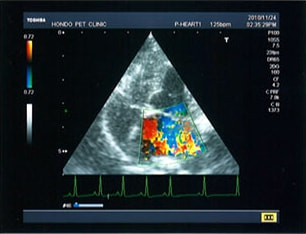

C:超音波画像 肺動脈領域の異常血流

D:左心系の拡張による二次的僧帽弁逆流

左側胸壁よりLevine 4/6の連続性心雑音が聴取された。胸部レントゲン検査において心拡大が認められ、超音波検査においても肺動脈領域に連続的な異常血流が観察された。大学病院を紹介受診され、手術が行われた。現在はACE阻害薬のみの内服で補助的治療を行っている。